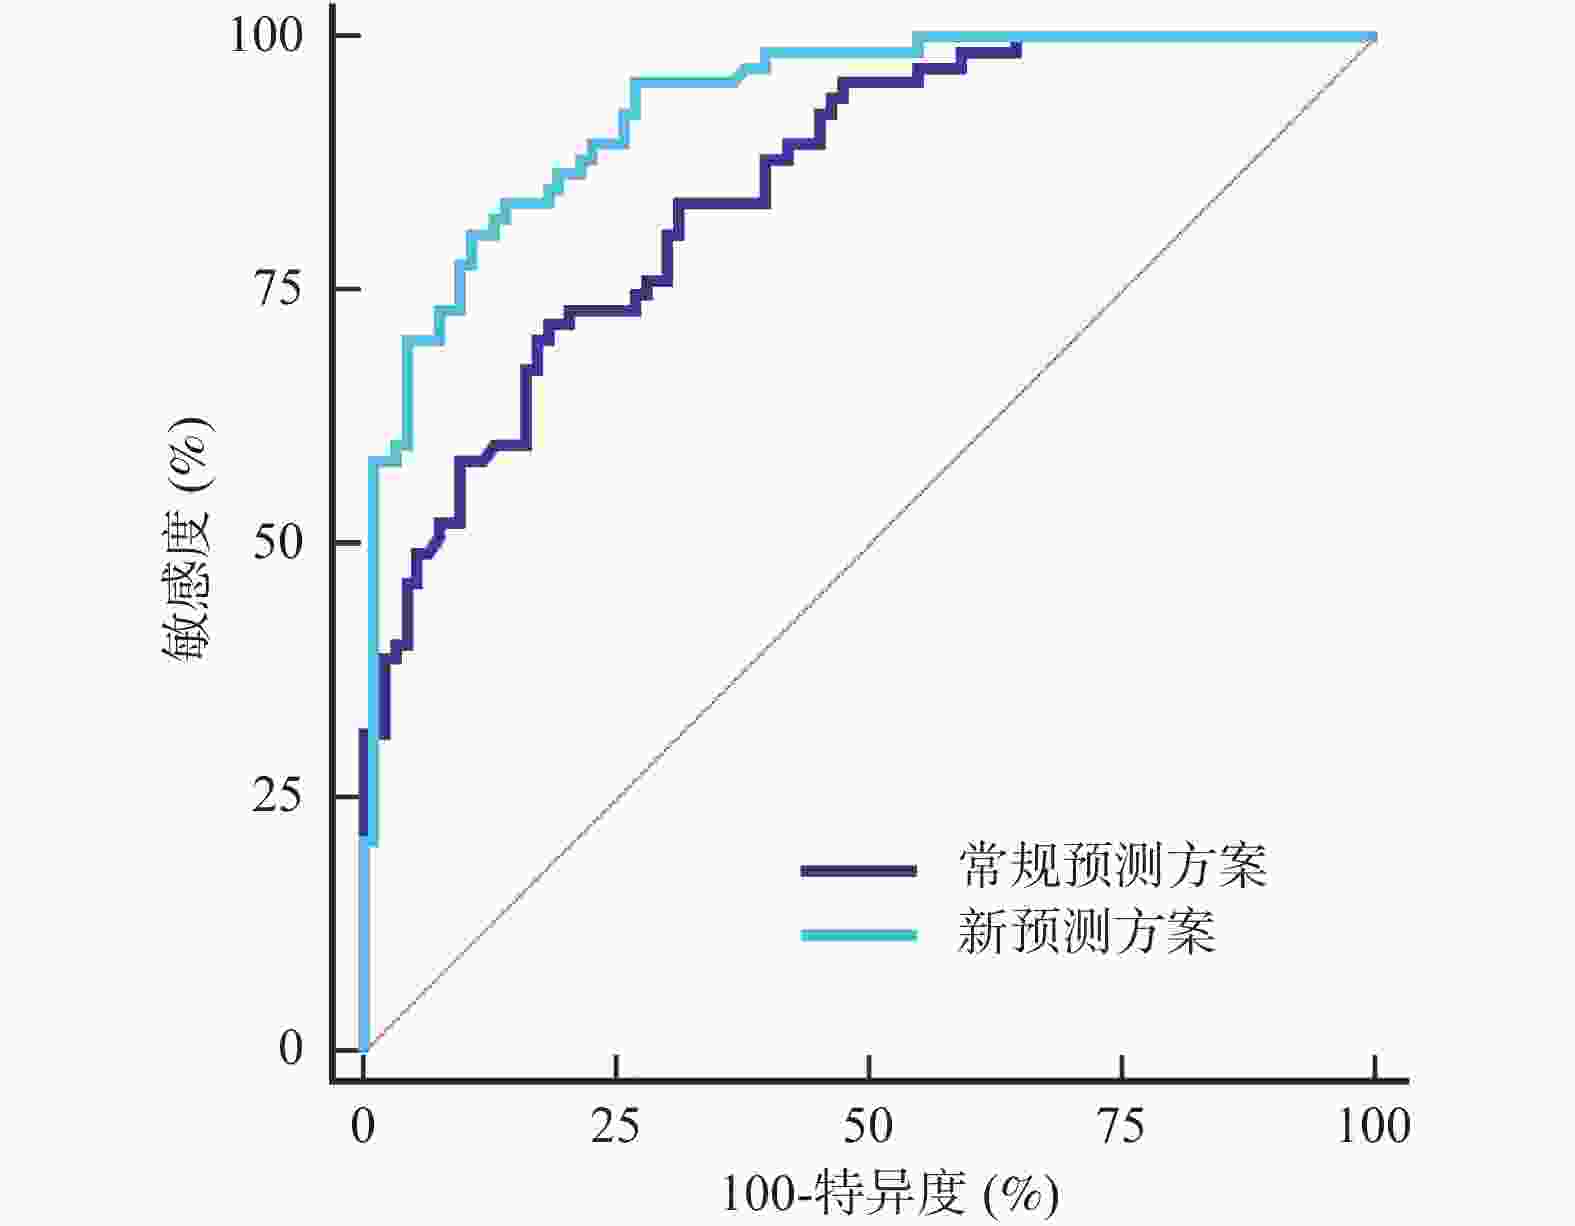

目的 探究肺部超声评分(LUS)、膈肌超声联合常规指标预测小儿重症肺炎(SP)并发急性呼吸窘迫综合征(ARDS)的价值。 方法 选取2022年8月至2023年8月昆明市儿童医院SP患儿160例,均行肺部超声、膈肌超声检查获取LUS、膈肌超声参数[膈肌移动度(DM)、膈肌厚度变化率(TF)],根据SP患儿住院期间是否并发ARDS分为ARDS组67例和非ARDS组93例,比较两组入院时一般资料、血清炎症因子水平、LUS、膈肌超声参数,分析SP患儿并发ARDS的影响因素,并分析LUS、膈肌超声参数预测SP患儿并发ARDS的价值。 结果 SP患儿住院期间ARDS发生率为41.88%(67/160);ARDS组入院时APS、APACHEⅡ评分、血清C反应蛋白(CRP)、白介素-6(IL-6)、高迁移率族蛋白B1(HMGB1)水平、LUS、DM高于非ARDS组,TF低于非ARDS组(P < 0.05);入院时APS、APACHEⅡ评分及血清CRP、IL-6、HMGB1水平、LUS、DM、TF均为SP患儿并发ARDS的影响因素(P < 0.05);LUS、DM、TF预测ARDS的曲线下面积(AUC)分别为0.718、0.742、0.720;常规预测方案(入院时APS、APACHEⅡ评分及血清CRP、IL-6、HMGB1水平联合)的AUC为0.852,新预测方案(常规预测方案基础上联合LUS、DM、TF)的AUC为0.930,新预测方案的AUC明显大于常规预测方案的AUC(P < 0.05)。 结论 LUS、膈肌超声参数DM、TF与SP患儿并发ARDS显著相关,联合常规指标可为临床预测SP患儿并发ARDS提供可靠依据。 Abstract:Objective To explore the value of lung ultrasound score (LUS) and diaphragm ultrasound combined with routine indicators in predicting the occurrence of acute respiratory distress syndrome (ARDS) in children with severe pneumonia (SP). Methods A total of 160 patients with SP were selected from Kunming Children’s Hospital from August 2022 to August 2023, all of whom underwent lung ultrasound and diaphragm ultrasound examination to obtain LUS and diaphragm ultrasound parameters [diaphragm mobility (DM), diaphragm thickness change rate (TF)]. The patients with SP were divided into ARDS group and non-ARDS group according to whether they were complicated with ARDS during hospitalization. The general data, serum inflammatory factor levels, LUS and diaphragm ultrasound parameters were compared between the two groups at admission, and the influencing factors of ARDS in children with SP were analyzed, and the value of LUS and diaphragm ultrasound parameters in predicting ARDS in children with SP was analyzed. Results The incidence of ARDS in SP patients was 41.88% (67/160). APS, APACHEⅡ scores, serum C-reactive protein (CRP), interleukin-6 (IL-6), high mobility group protein B1 (HMGB1) levels, LUS and DM in ARDS group were higher than those in non-ARDS group, TF were lower than those in non-ARDS group (P < 0.05). APS, APACHEⅡ scores, serum CRP, IL-6, HMGB1 levels, LUS, DM, TF were the influencing factors of ARDS in SP children at admission (P < 0.05). The area under the curve (AUC) of LUS, DM and TF predicted ARDS were 0.718, 0.742 and 0.720, respectively. The AUC of the conventional prediction scheme (APS, APACHEⅡ score combined with serum CRP, IL-6 and HMGB1 levels at admission) was 0.852, while that of the new prediction scheme (combined with LUS, DM and TF based on the conventional prediction scheme) was 0.930. The AUC of the new prediction scheme was significantly higher than that of the conventional prediction scheme (P < 0.05). Conclusion LUS, DM, TF, and SP parameters of the diaphragm are significantly correlated with ARDS in children with SP, and the combination of routine indicators can provide reliable evidence for clinical prediction of ARDS in children with SP. -

Table 5. Comparison of the value of different prediction schemes in predicting ARDS in children with SP

成对对比 AUC差异 标准误差 95%CI上限 95%CI下限 Z P 新预测方案vs常规预测方案 0.079 0.032 0.141 0.014 2.400 0.016* *P < 0.05。 -